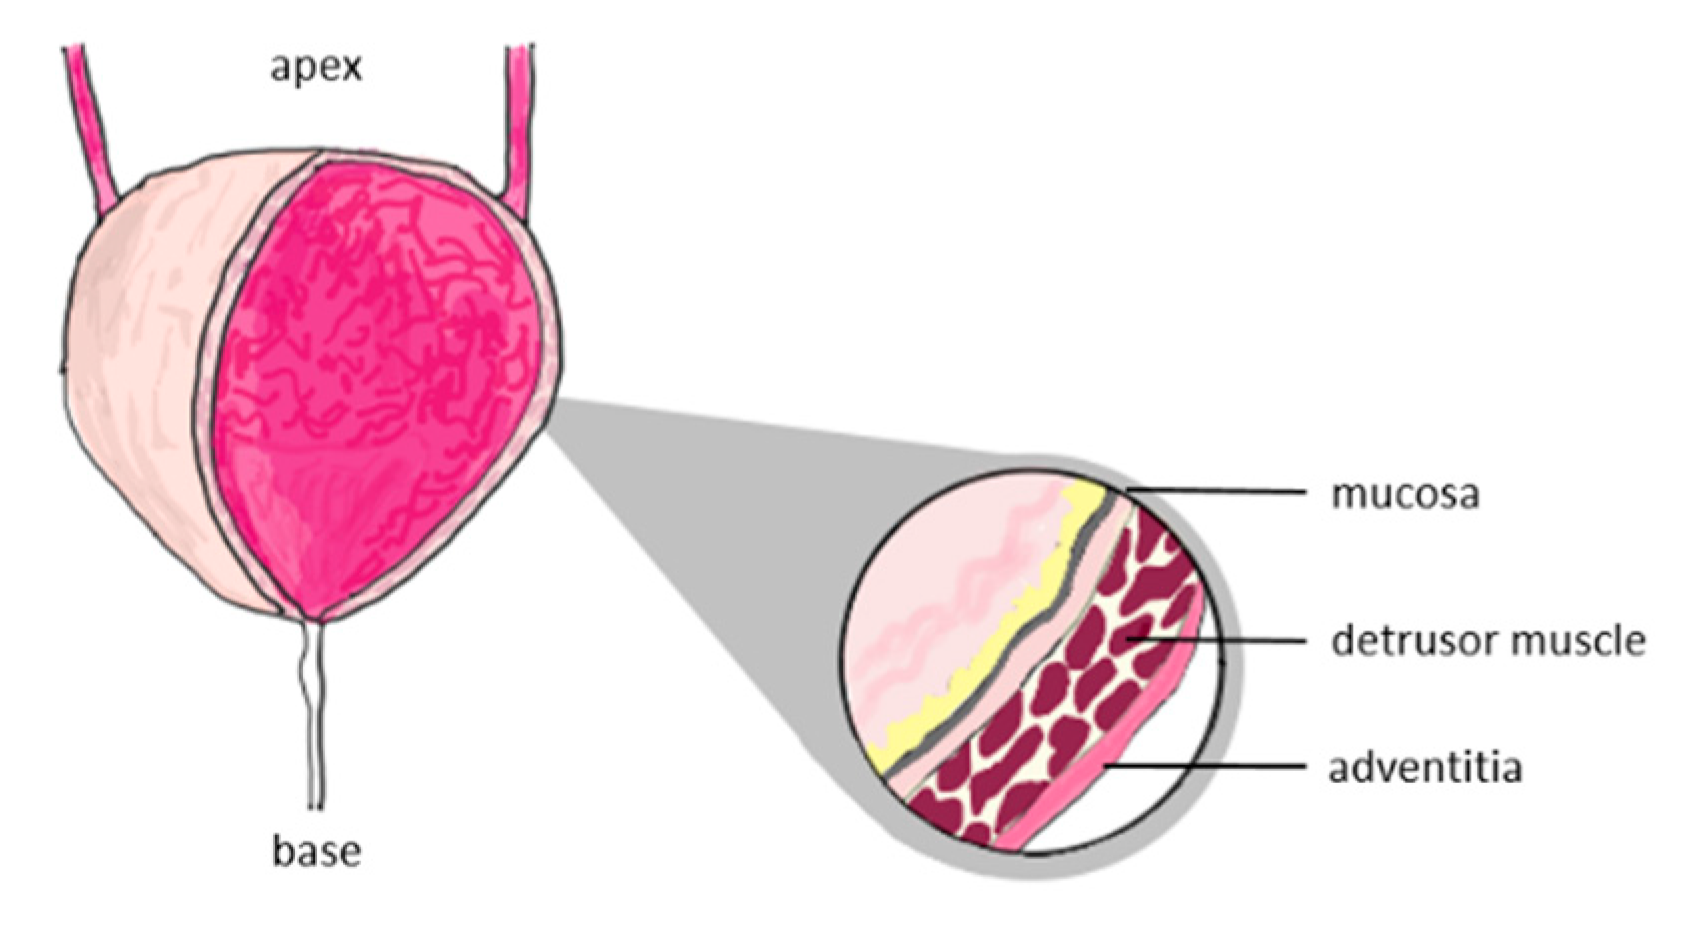

- Korossis, S.; Bolland, F.; Eileen Ingham; John Fisher; John Kearney; Jennifer Southgate. Review: Tissue Engineering of the Urinary Bladder: Considering Structure-Function Relationships and the Role of Mechanotransduction. Tissue Engineering 2006, 12(4), 635-44.

- Hanczar, M.; Moazen, M.; Day, R. The Significance of Biomechanics and Scaffold Structure for Bladder Tissue Engineering. Int J Mol Sci. 2021, 22(23), 12657. [Google Scholar] [CrossRef] [PubMed]